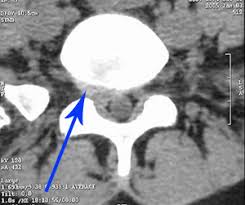

所以必須利用更精密的電腦斷層掃描檢查 (CT) ,顯現椎間盤突出有無壓迫影響到神經,另外醫師可能加作脊髓腔造影,需在蜘蛛膜下腔注射入顯影劑,如此可以加強脊索及神經根之影像,增加診斷之正確性。

現在醫師也可能是安排磁振造影檢查 (MRI) ,可將脊椎、脊髓、神經根、軟骨等 結構顯露無遺,找出那個部位有椎間盤突出 . 此項檢查就不需要打顯影劑。